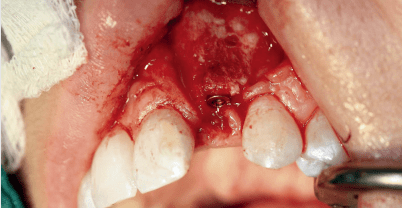

Die Patientin hatte eine komplexe, breite, linksseitige Lippen-, Kiefer-, Gaumenspalte, die verschlossen wurde. Im Alter von zehn Jahren erfolgte eine Kieferspaltosteoplastik. Nach Abschluss der eigentlichen Spaltchirurgie und der kieferorthopädischen Behandlung bestand bei der inzwischen 17-jährigen jungen Frau eine Schaltlücke in Regio 22 und stark vernarbtes Gewebe im Vestibulum (Abb. 1). Die Breite der Schaltlücke betrug 5,5mm. Ferner bestand eine deutliche Knochenatrophie. Zusätzlich stellte sich ausgeprägt vernarbtes Weichgewebe vestibulär bei dysgnather intermaxillärer Beziehung dar.

Primär erfolgte eine Umstellungsosteotomie im Oberkiefer zur Verbesserung der intermaxillären Beziehung. Vier Monate später wurde im Zuge der Entfernung des Osteosynthesematerials eine Re-Augmentation des Kieferspalts mit einem autologen Beckenkammtransplantat vorgenommen. Die Fixierung erfolgte mit Osteo­syntheseschrauben (Abb. 2). Um das Knochentransplantat gut einheilen zu lassen, jedoch nicht das Risiko einer Atrophie einzugehen, erfolgte drei Monate später das Entfernen dieser Schrauben (Abb. 3). In Vorbereitung der Implantation wurden ein DVT und eine Bohrschablone angefertigt. Interoperativ zeigte sich ein reizlos eingeheiltes Knochentransplantat (Abb. 4). Aus diesem Grund ist im Zuge dieses Eingriffes ein XiVE®-Implantat mit 3,0mm Durchmesser und 15mm Länge gesetzt worden. Das Implantat war primärstabil und gänzlich knöchern gefasst (Abb. 5). Aufgrund der quantitativ guten knöchernen Verhältnisse ließen sich die Insertionsvorgaben entsprechend des Buserprotokolls einhalten.